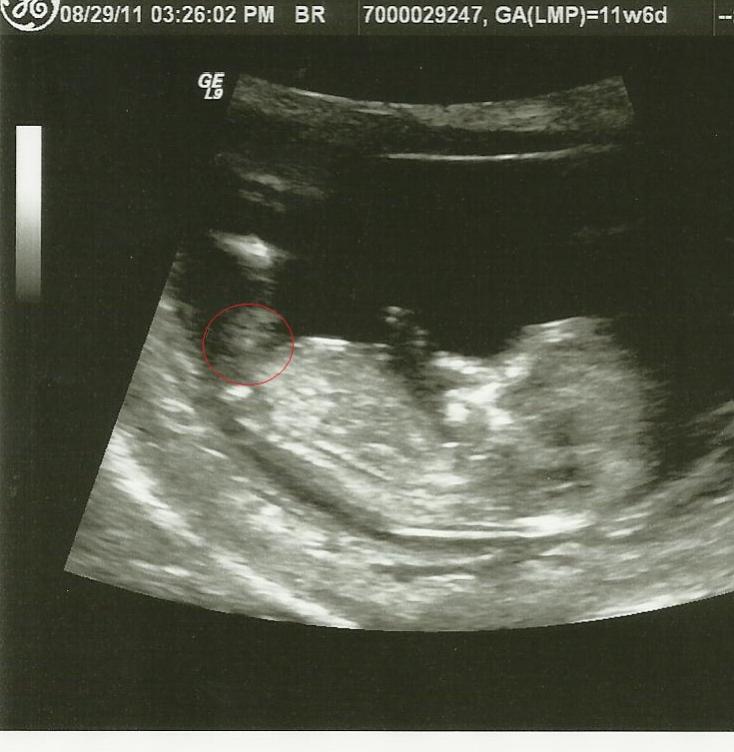

there seems to be a very faint nub but it looks kinda big to mAttachment 585e? what do guys think my gender scan is tomorow

Is there any chance of Girl it looks flat to me but does shape matter\? is that even the nub?

Please guess>>>